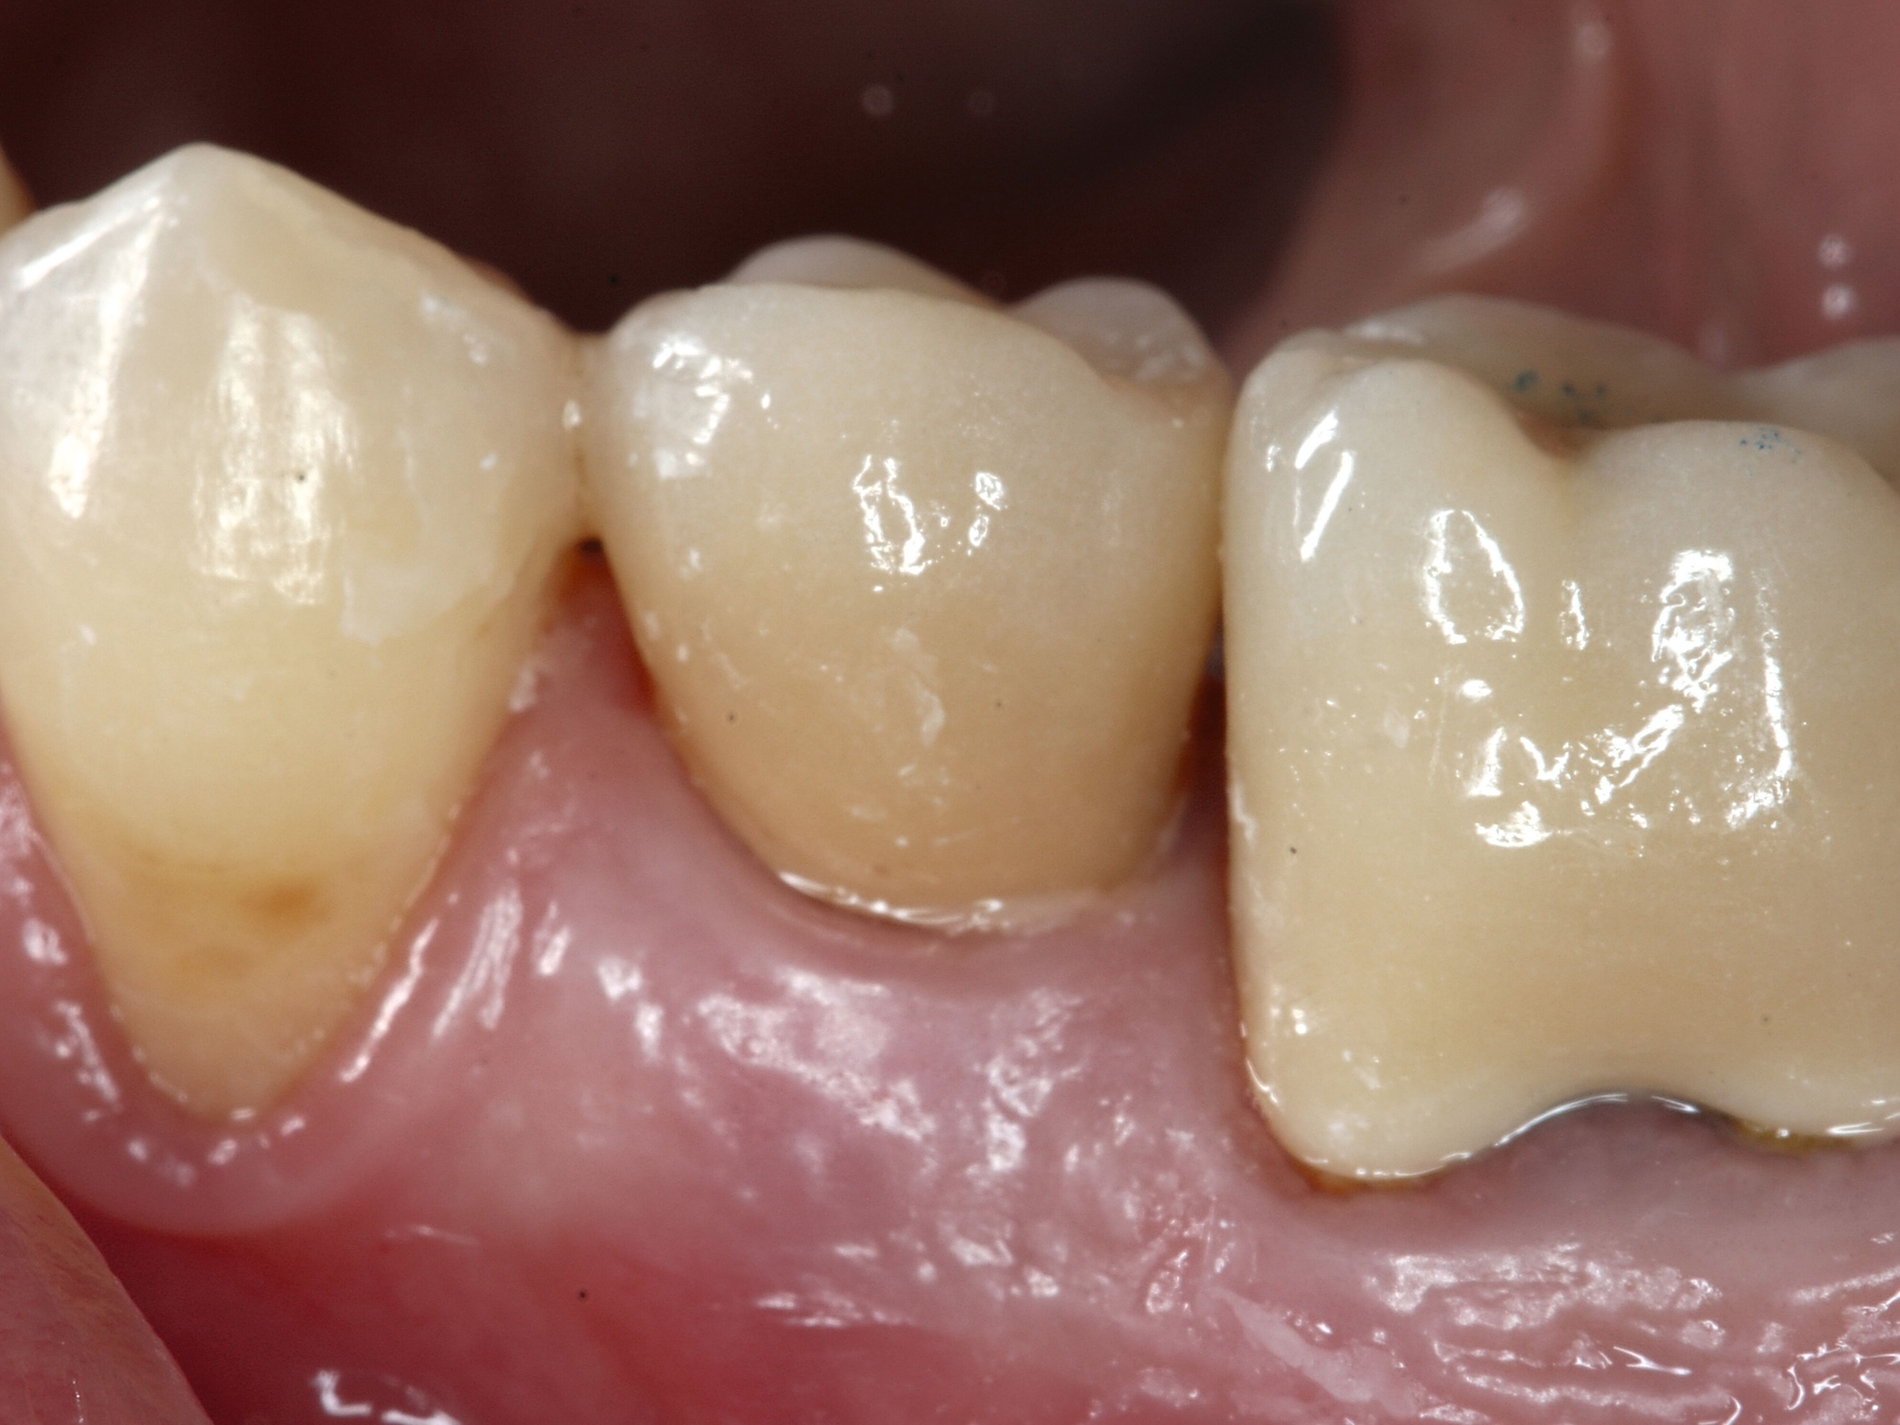

Schnelle kieferorthopädische Extrusionen im Sinne einer präprothetischen Maßnahme können zudem auch im Seitenzahnbereich indiziert sein, wenn für eine nachfolgende Kronenversorgung die notwendigen Voraussetzungen geschaffen werden sollen (ausreichende Stumpfhöhe, Einhaltung der biologischen Breite, Schaffung des Ferrule-Designs) [Gariulo et al., 1961; Juloski et al., 2012; Nugala et al., 2012] unter Einhalten eines Kronen-Wurzel-Verhältnisses von 1:1 [Grossmann und Sadan, 2005] (Abbildung 3).